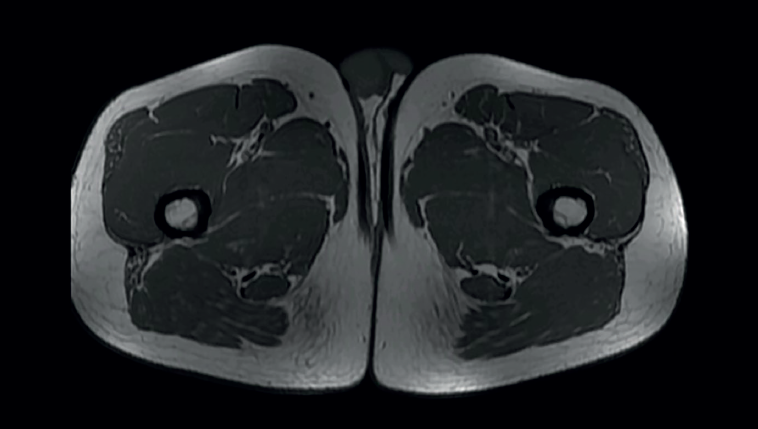

Figure 3. Axial (T1) view of the thighs, showing the typical "comma" image of the rectus femoris of both quadriceps.